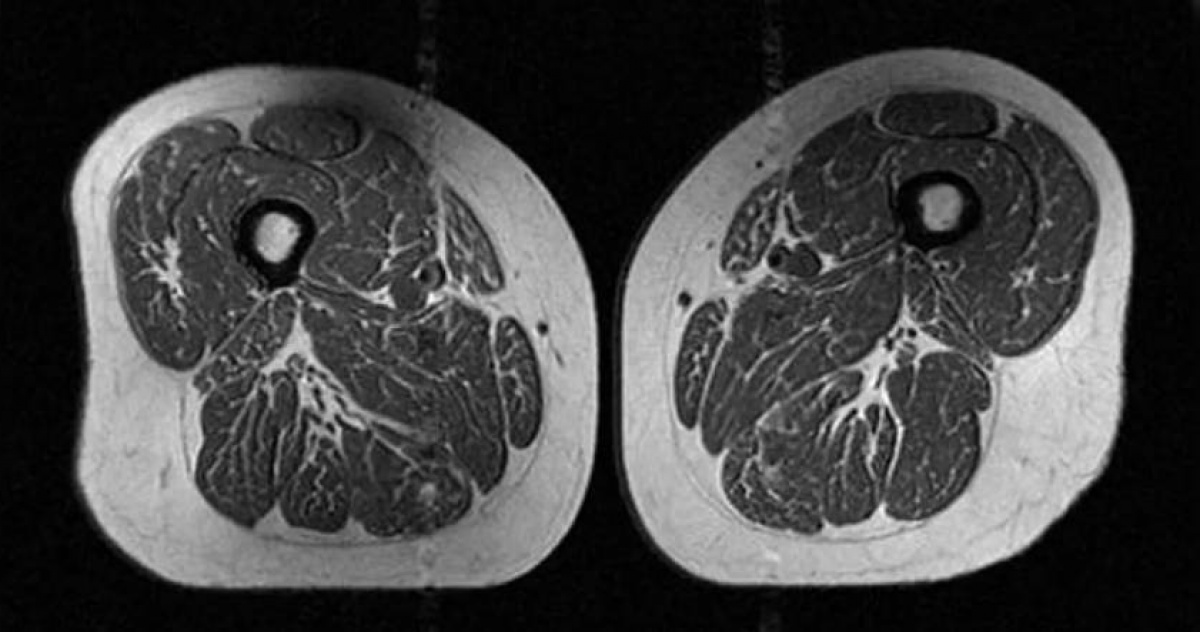

標題: 大腿肌肉變「A5和牛」! 研究:小心吃太多超加工食品

超加工食品

大腿

肌肉脂肪

膝關節